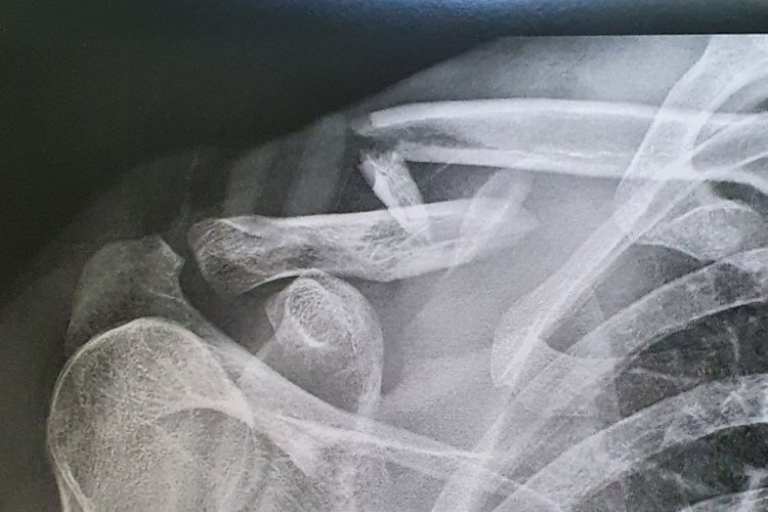

Beim Superbike-Meeting in Misano zog sich Chris Ponsson bei einem Sturz im ersten Lauf einen komplexen Schlüsselbeinbruch zu. Röntgenbilder belegen den desaströsen Zustand der Knochen, die Operation war schwierig.

Mit einem mehrfachen Schlüsselbeinbruch war das vierte Saisonmeeting für den Franzosen vorzeitig beendet, doch er muss auch um seine Teilnahme am Meeting in Donington Park am 16./17. Juli bangen. Denn die zur Fixierung des Knochens erforderliche Operation war aufwendig. "Es war kein einfacher Schlüsselbeinbruch", sagte der nur scheinbar gut gelaunte Ponsson. "Bevor die Rekonstruktion mit einer Platte und zehn Schrauben möglich war, mussten Muskeln und Nerven durchtrennt werden, um die Knochenstücke wieder an die richtige Stelle zu platzieren. Ich arbeite jeden Tag mit meinem Physiotherapeuten, um in etwas mehr als zwei Wochen für das nächste Rennen in England so gut wie möglich wieder fit zu sein." Der 26-jährige Ponsson fährt seine zweite Saison mit der Yamaha R1. Den im letzten Drittel 2021 gezeigten Aufwärtstrend konnte er in diesem Jahr nicht fortsetzen und belegt mit 8 WM-Punkten den 22. WM-Rang.